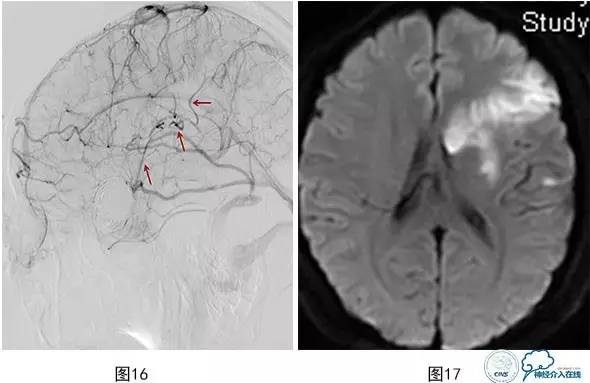

将微导管超选入载瘤动脉注入替罗非班10ml(图13),导引导管内注入替罗非班5ml,血流再通(图14)。术后患者神清,对答切题,伸舌左偏,四肢可遵嘱活动,肌力5级,即刻予以阿司匹林300 mg,氯吡格雷150mg口服。术后20 min,运动性失语,反应迟钝,右侧肢体无力,右上肢肌力0级,右下肢肌力2+,左侧肢体能遵嘱活动,即刻复查颅脑数字减影血管造影(DSA)示:大脑中动脉下干支架内血栓形成,远端血流缓慢(图15)。机械碎栓,部分再通,微导管在上下干开口处2h内分次注入替罗非班共40ml,上干再通,下干分支部分再通,远端可通过软膜吻合显影(图16)。术后患者症状缓解,右侧肢体肌力4+,面瘫消失,部分运动性失语,术后替罗非班静脉微泵维持48h,术后维持收缩压120mmHg以上。术后头颅磁共振弥散加权成像(MR DWI)示左侧大脑中动脉供血区急性梗塞灶(图17)。

图16 大脑中动脉上干再通,下干分支中一支再通,一支血流缓慢,远端可通过软膜吻合显影

图17 术后MR DWI示左侧大脑中动脉供血区急性梗塞灶